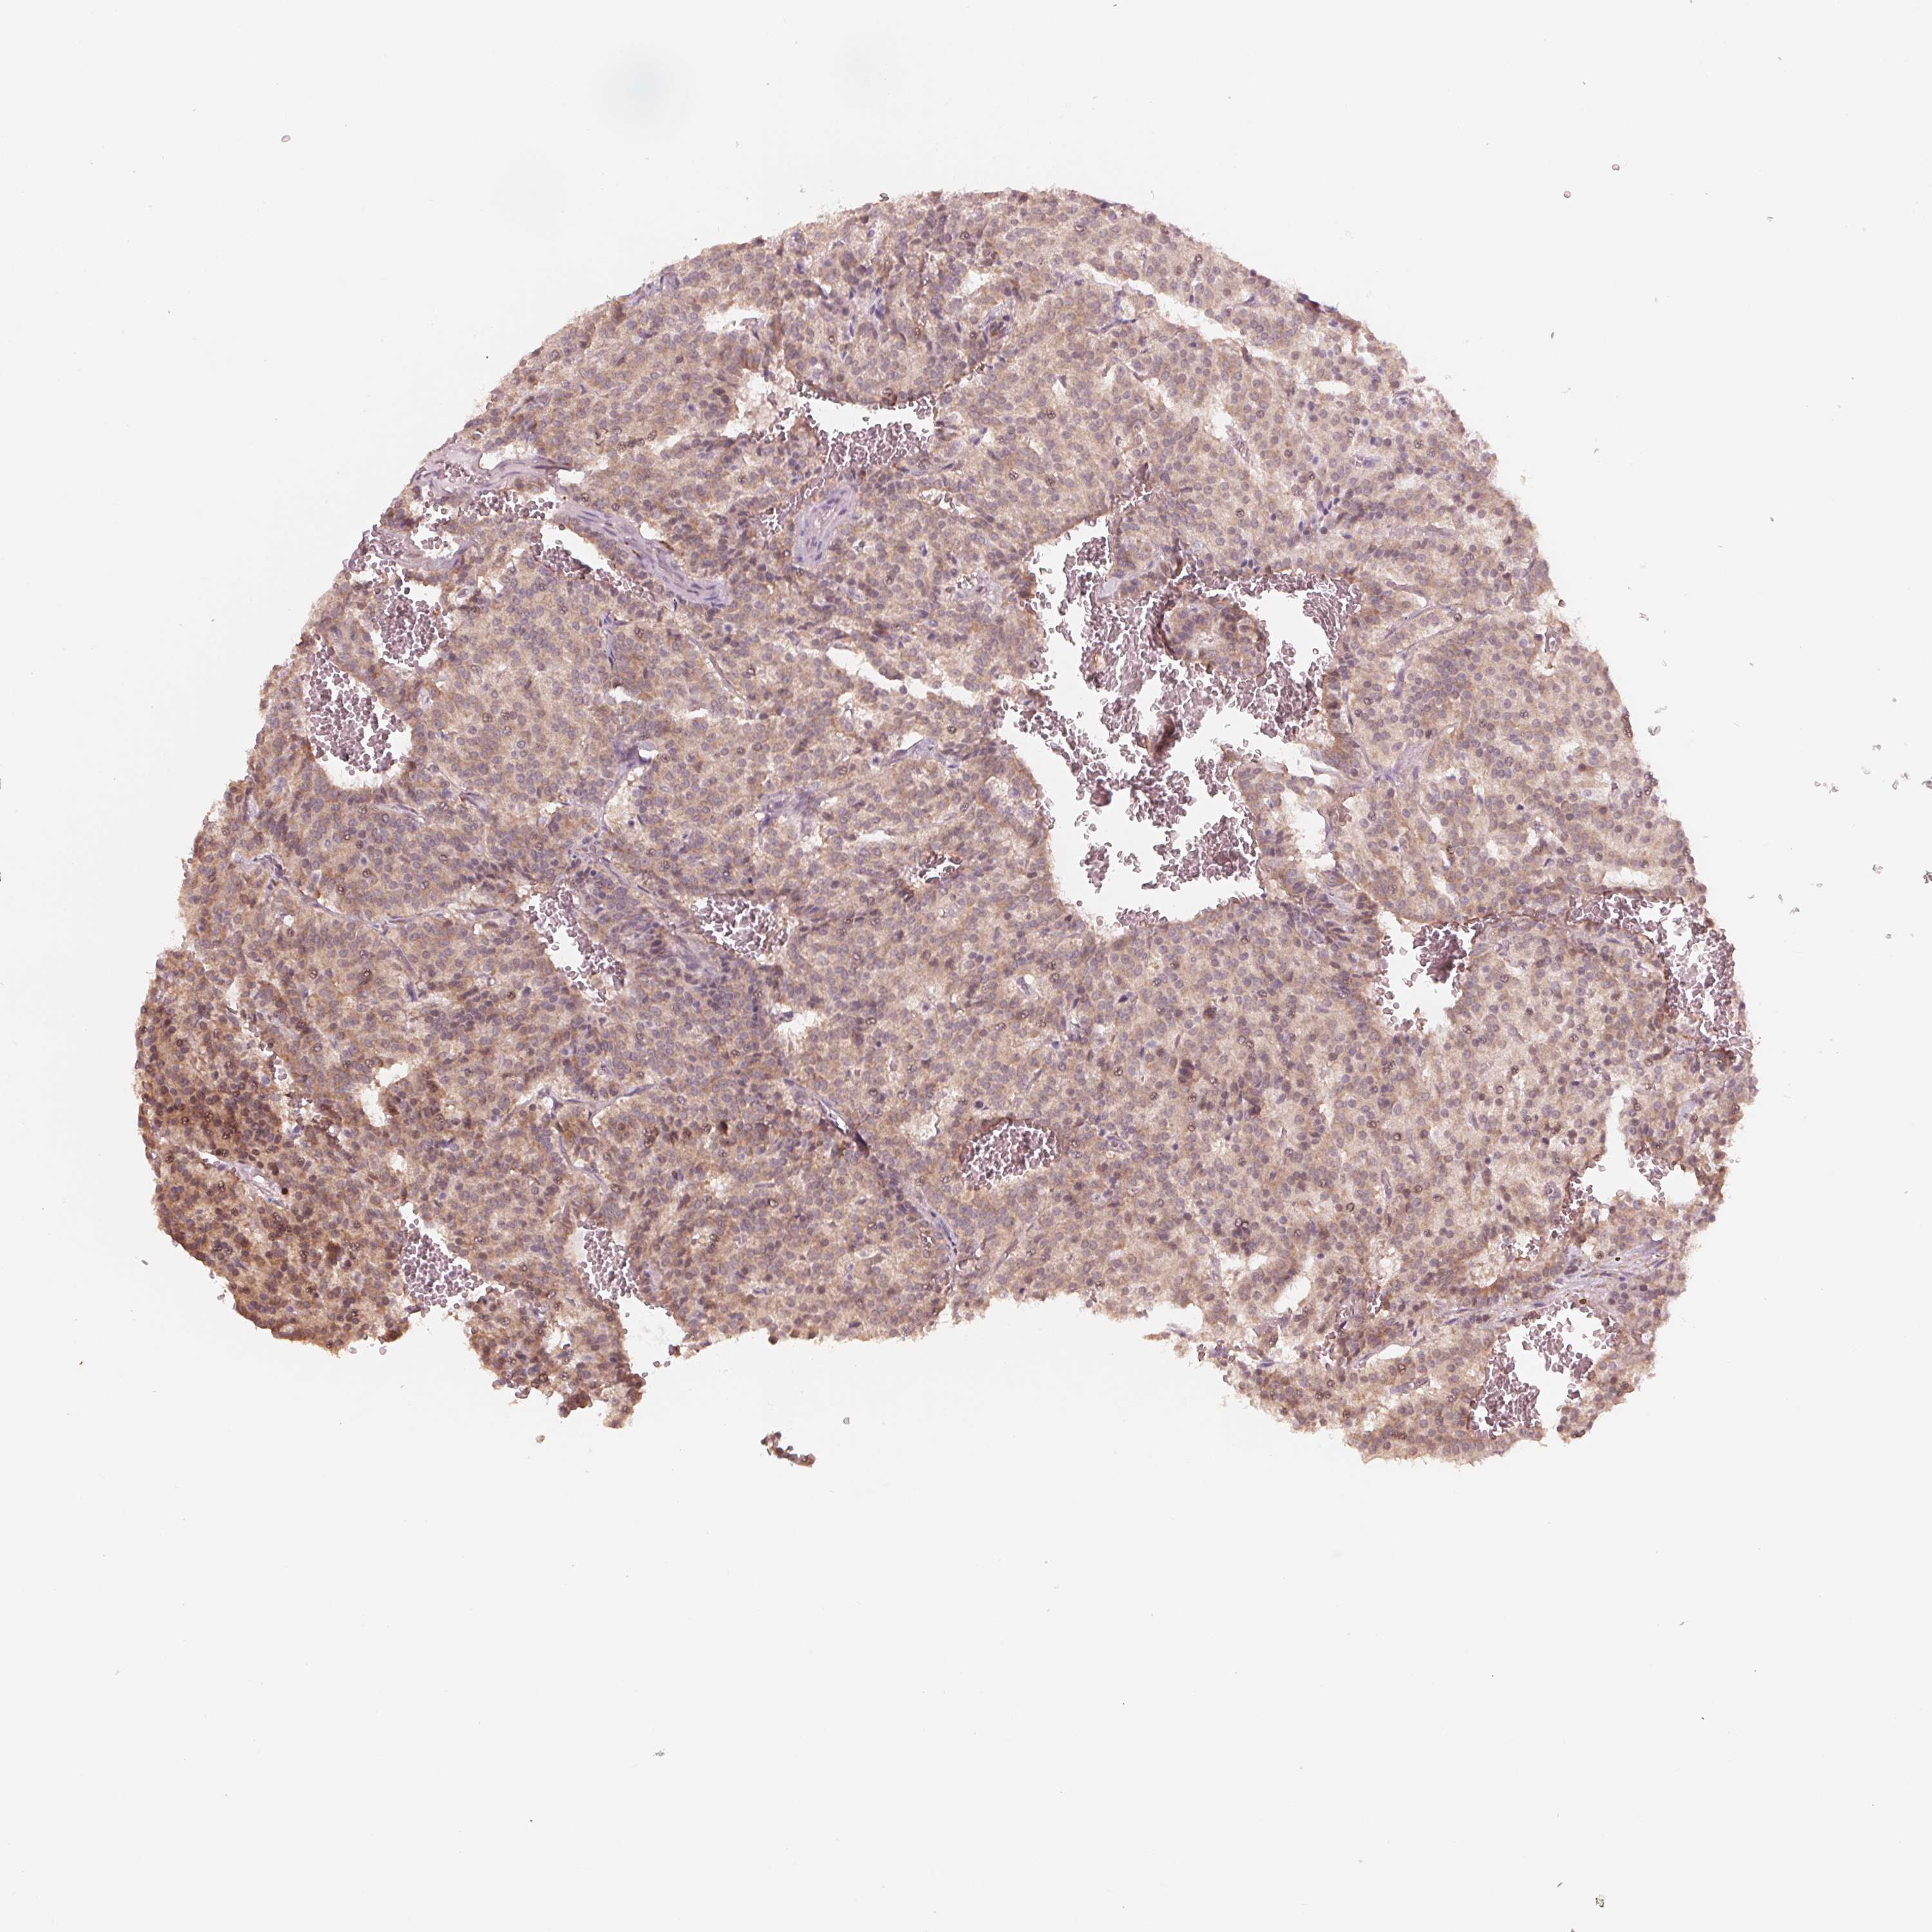

CARCINOID - Protein expressioni

A mouse-over function shows sample information and annotation data. Click on an image to view it in a full screen mode. Samples can be filtered based on level of antibody staining by selecting one or several of the following categories: high, medium, low and not detected. The assay and annotation is described here.

Antibody stainingi

Antibody staining in the annotated cell types in the current human tissue is reported as not detected, low, medium, or high, based on conventional immunohistochemistry profiling in selected tissues. This score is based on the combination of the staining intensity and fraction of stained cells.

Each image is clickable and will lead to virtual microscopy that enables deeper exploration of all samples and also displays staining intensity scores, fraction scores and subcellular localization as well as patient and tissue information for each sample.

Antibody HPA059918

Carcinoid, malignant, NOS